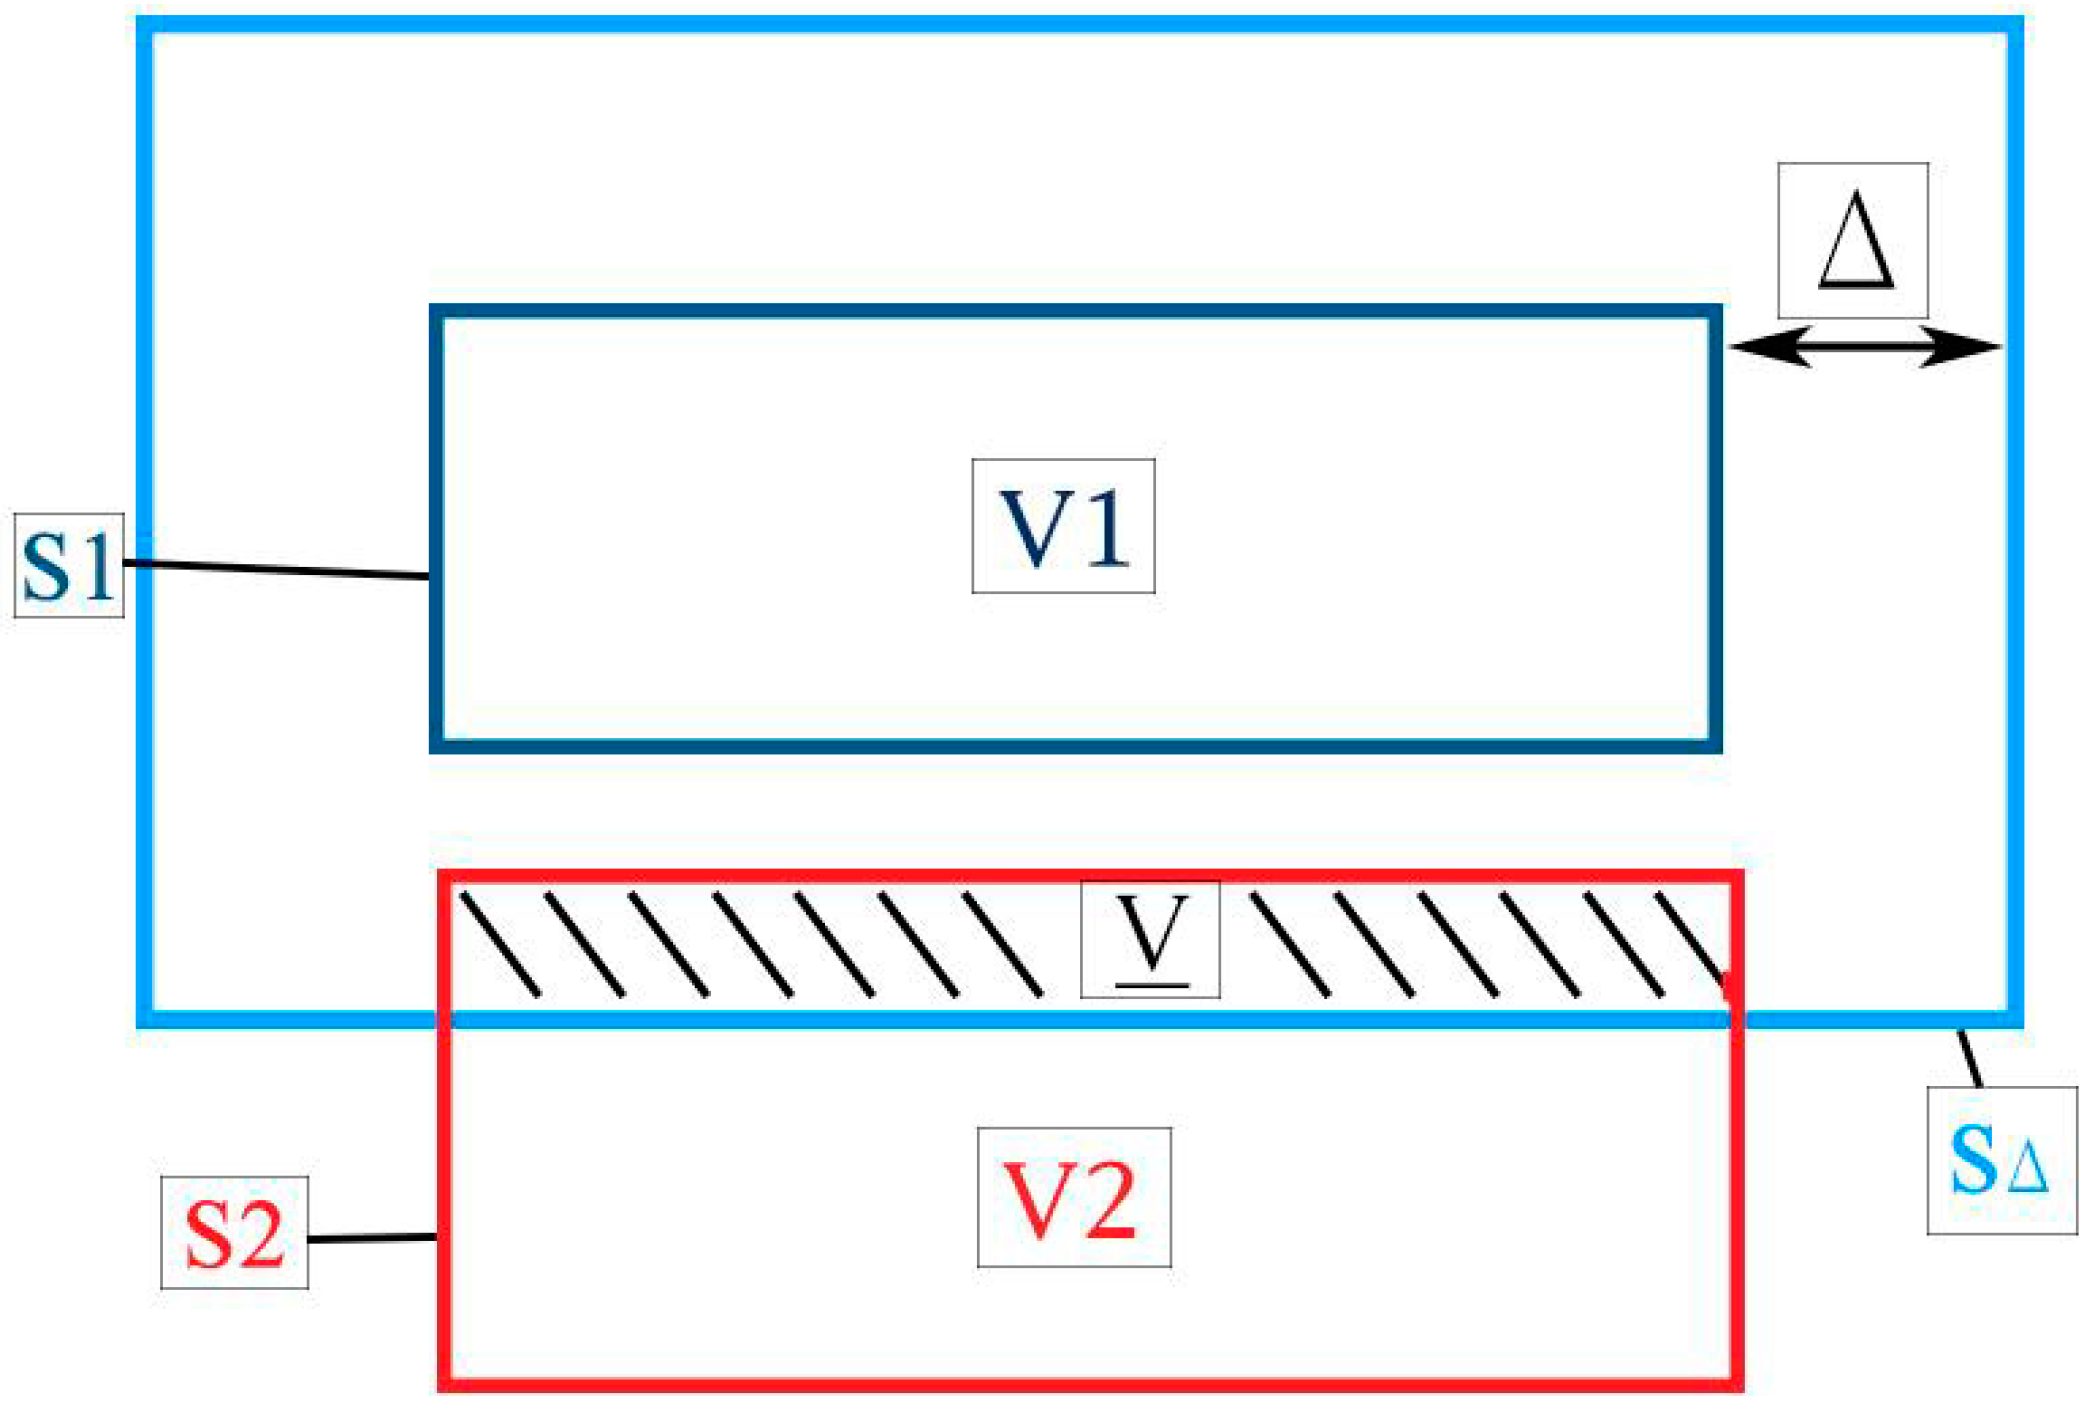

2.1. Joint Congruence and Contact Model